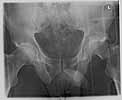

49 year old male, active speedskater, one year after MVC with multiple trauma and mild traumatic brain injury. Pipkin type IV fracture of the left hip. Same day ORIF through KL approach. No heterotopic ossification "prophylaxis". Day 7 wound revision for hematoma. Full weightbearing after 3 months. Full recovery except left hip function due to early severe HO. Function after one year: fixed ankylosis in 40 degrees flexion, 10 degrees exorotation. Patient frequently asks for attempt to improve hip function.

Post Op - Click to Magnify